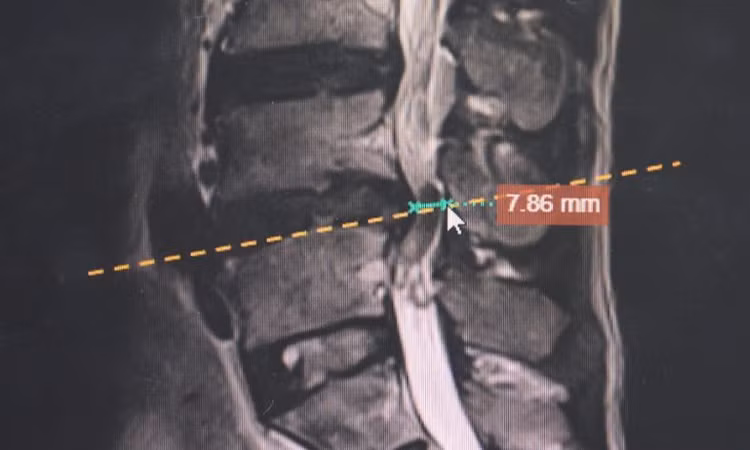

| Ảnh chụp MRI thoát vị đĩa đệm của người bệnh. Ảnh BVCC |

Tại bệnh viện, hình ảnh chụp cộng hưởng từ cho thấy khối thoát vị đĩa đệm chèn ép mạnh vào rễ thần kinh thắt lưng.